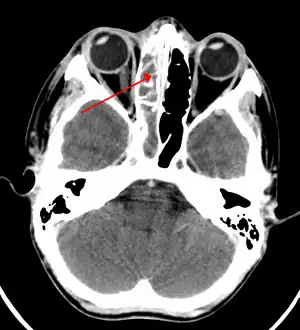

A CT scan showing sinusitis of the ethmoid sinus

For sinusitis lasting more than 12 weeks, a CT scan is recommended.[47] On a CT scan, acute sinus secretions have a radiodensity of 10 to 25 Hounsfield units (HU), but in a more chronic state they become more viscous, with a radiodensity of 30 to 60 HU.[49]